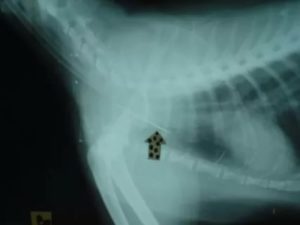

Иногда даже врач-ЛОР не всегда может визуально определить местонахождения косточки. Чтобы найти такую рыбью кость, необходимо сделать снимок, иногда даже нужно делать ФГДС пищевода.